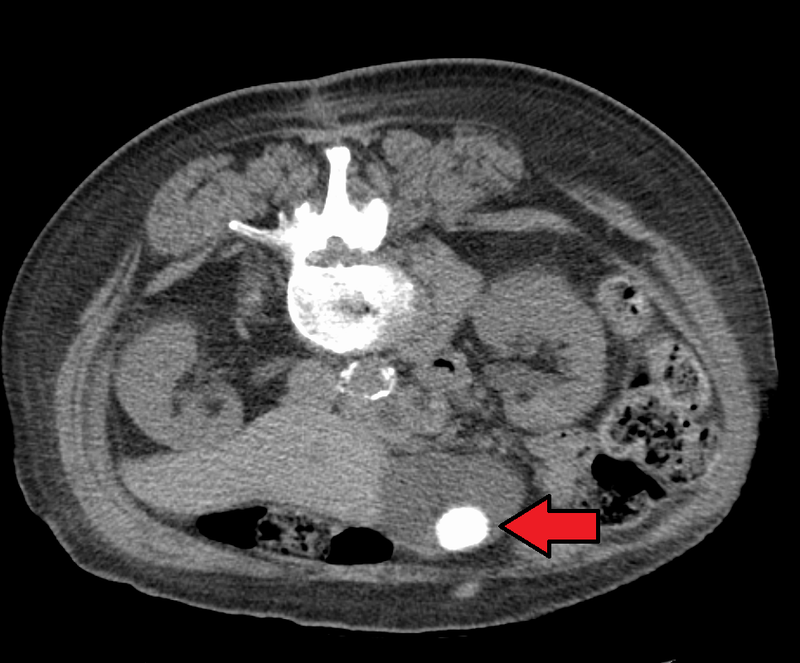

Gallstone Ileus

Gallstone ileus occurs when the small bowel is obstructed by a gallstone.

A predisposition to gallstone ileus may occur because of fistula formation between the small bowel and gallbladder as a result of cholecystitis.